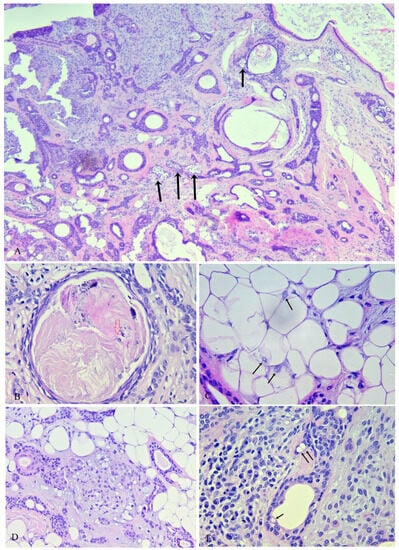

3. Histopathologic Assessment